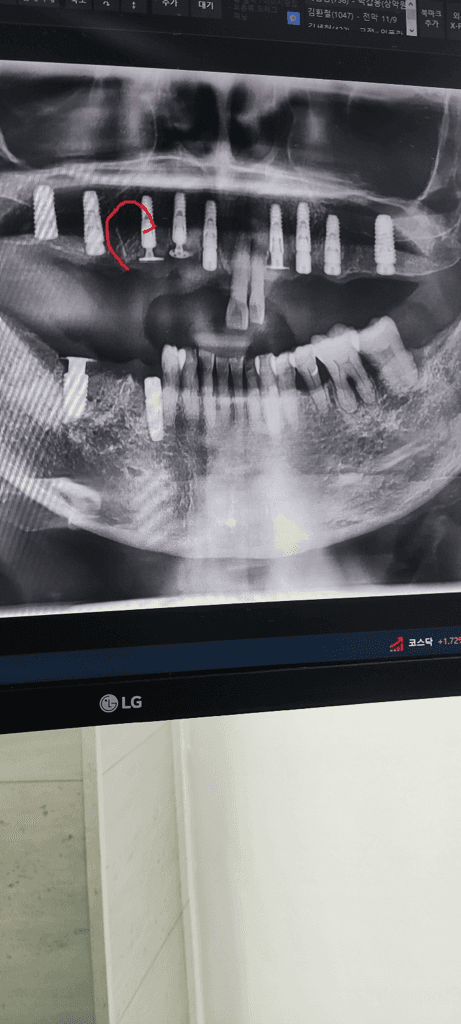

임플란트 자체의 문제보다는 임플란트를 감싸고 있는 뼈 부분에서 날카로운 부분이 있는 것으로 보여집니다. 2차 수술을 할때 해당 부분을 다듬어주면 큰 문제는 없어 보이나 정확한 판단을 위해서는 x-ray 사진이나 ct 등을 통해 평가가 필요해보입니다.

치열을 발치하고 나서는 특정 부위의 잇몸이 날카롭게 올라와 있는 경우 통증이 있을 수 있습니다. 이런 잇몸은 간단하게 다듬어 줄 수 있기 때문에 치과에서 진료를 받아보는 것이 좋습니다.

잇몸뼈가 과하게 성장된경우에는 추후에 잇몸뼈를 삭제하면됩니다. 너무 걱정은 안하셔도 될것같습니다.

네 돌출된 뼈 부분은 잇몸 열고 나중에 조금 갈아내서 모양을 부드럽게 만들어주면 되므로 큰 문제는 아닙니다